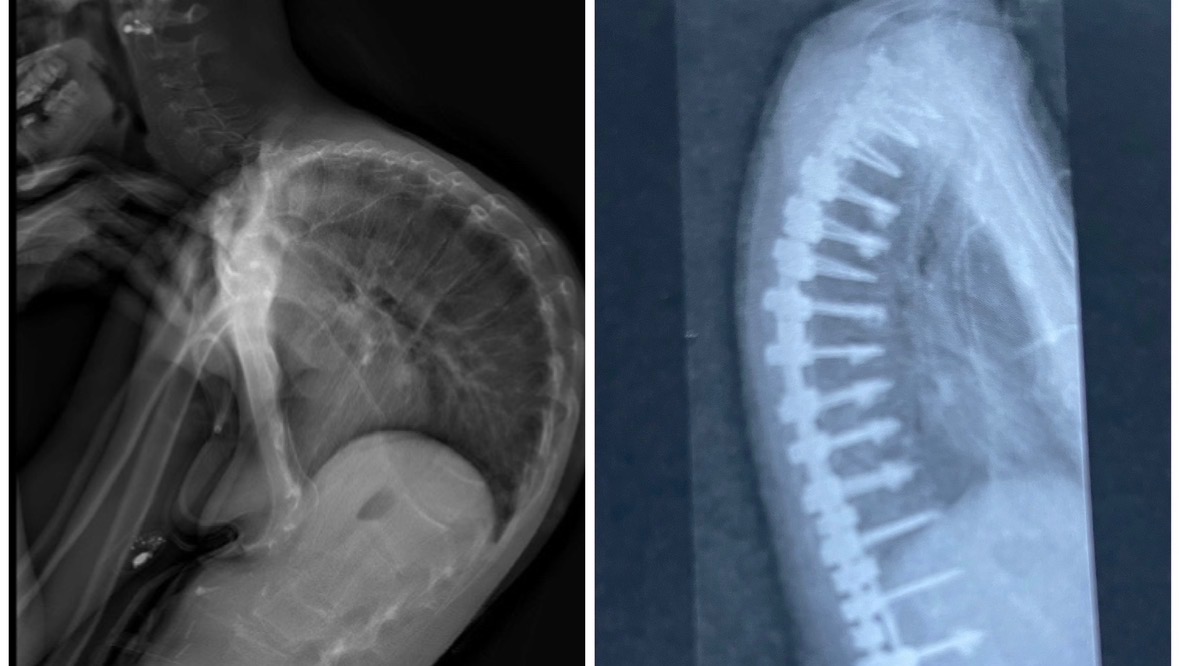

Annie has endured countless life-threatening procedures and surgeries, lived with invasive tubes that keep her body alive, and suffered extreme side effects from the very medications she depends on to survive.

For more than a decade, Annie has received all of her nutrition through TPN (Total Parenteral Nutrition) — a central line in her chest that feeds directly into her bloodstream.

Annie has survived sepsis 25 times, lives with chronic, debilitating pain, has suffered multi-organ failure, severe osteoporosis and fractures, and has missed out on so many milestones most of us take for granted, simply because she was fighting to stay alive.